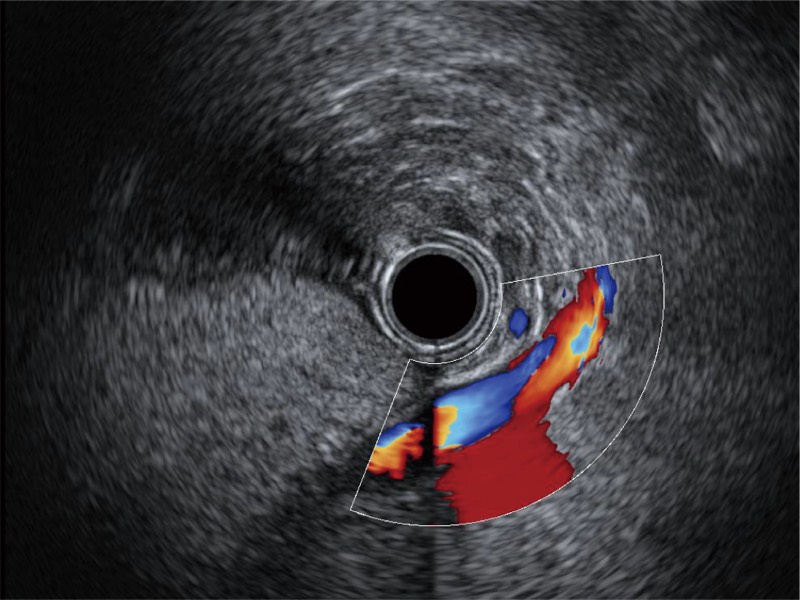

清晰显示胆总管及周围血管分布

肝左叶和肝静脉的横截面